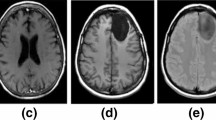

Brain tumour is a lump of tissue produced by uncontrolled growth of cells in the human brain. Automated and accurate detection of brain tumour is important for robotics based surgery operation. The proposed method enhances the accuracy, sensitivity and specificity of automated brain tumour detection by adopting an accurate two phase method of detection. The method segments the Axial plane slices of Magnetic Resonance image in its first phase. In the second phase, binary decision values representing the presence or absence of tumor cells on each pixel locations are projected into 3D space to obtain the 3D tumor. Contrast Enhanced fuzzy c-means (CEFCM) clustering method is used to segment the 2D tumor regions from MR image slices due to its high accuracy. The decision values obtained from the segmented image for each pixel locations are mapped into 3D space using Pixel based voxel mapping technique (PBVMT). Average accuracy (Dice overlap coefficient) and average sensitivity of detection are measured with respect to the given ground truth of the image of BRATS 2013 dataset. The overall accuracy, sensitivity and specificity of detection are found to be 0.948, 92.14% and 96.97% respectively.